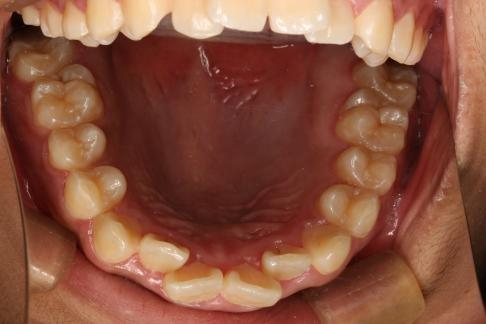

舌弓保持替牙间隙并隐形矫正排齐牙齿。